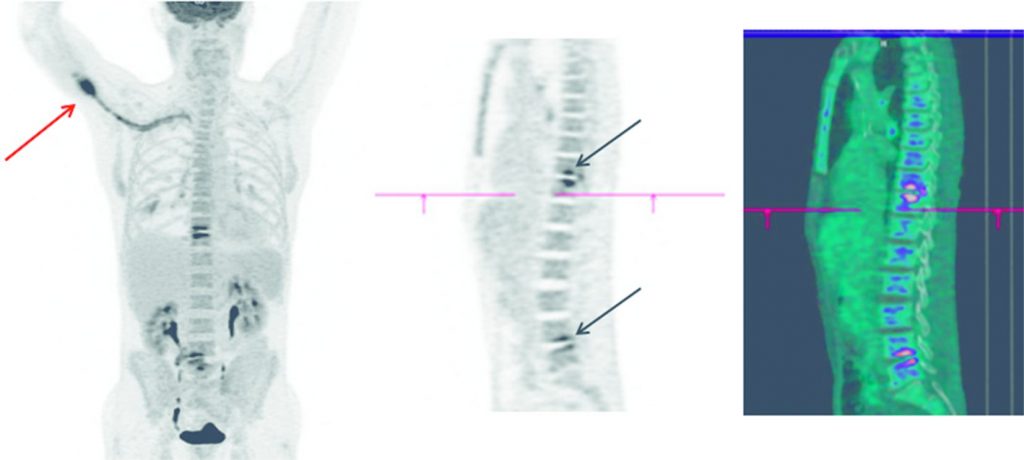

D. TEP-TDM au 18FDG

- Hyperfixations linéaires en miroir des espaces intervertébraux évocateurs de foyers de spondylodiscite.

- Associées parfois à des hypermétabolismes des structures adjacentes (muscle, graisse) évoquant une infiltration des parties molles (figure 78.5).

Fig. 78.5 En TEP-TDM au 18FDG : image en MIP 3D (A), en coupes sagittales TEP (B) et TEP couplée à la TDM (C).

Mise en évidence d’hypermétabolismes pathologiques des disques intervertébraux T10-T11 et L4-L5 en rapport avec deux foyers de spondylodiscite (flèches noires). Hypermétabolisme pathologique de la picc line (flèche rouge) évoquant une porte d’entrée à ce niveau.

Source : CERF, CNEBMN, 2022.